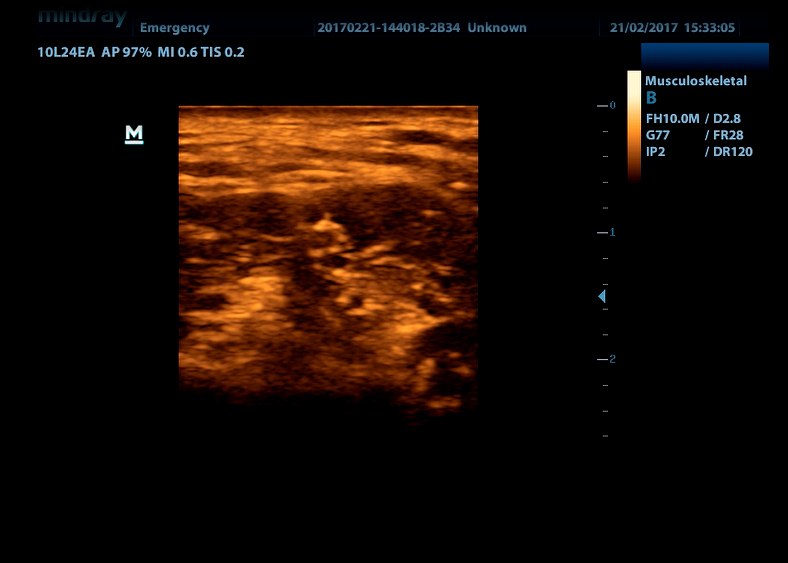

iBeam Позволяет использовать несколько углов сканирования для формирования единого изображения, что приводит к увеличению контрастного разрешения и улучшению визуализации.

iClear Позволяет улучшить качество изображения, основываясь на автоматическом распознавании структур.

- Более четкие края и контуры

- Плавное и однородное отображение тканей

- Снижение зернистости в «областях без эхосигнала»